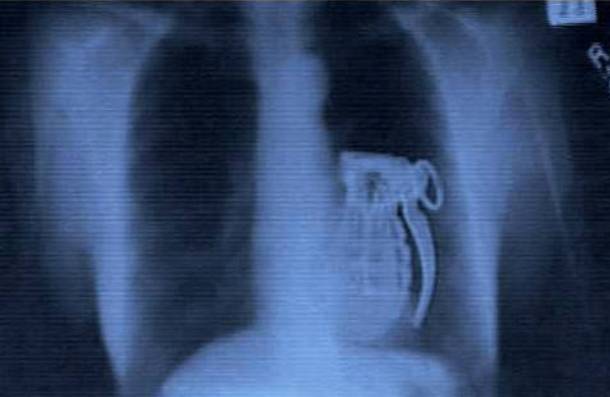

1. X-Ray of a Suicide Bomber

*All images sourced from Reddit*This is a hand grenade inside a stomach of someone who was a suicide bomber. He had planned to trigger the bomb as a part of an attack - but, the plan thankfully did not work as once the bomb was inside his stomach he had no way of triggering it...Advertisement